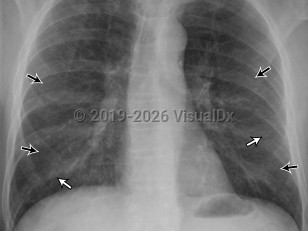

Pneumothorax

Spontaneous pneumothoraxSpontaneous pneumothorax

Tension pneumothorax